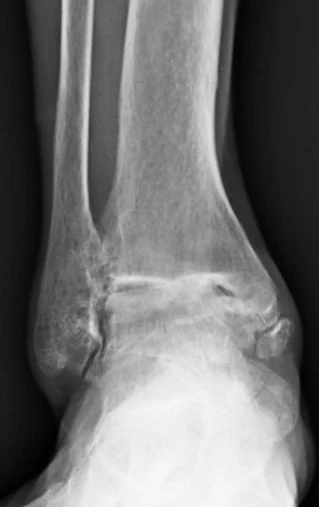

Complete Guide to Ankle Arthritis: Your Treatment Options Explained

Ankle arthritis can make every step painful, but treatment options go far beyond “just live with it.” From braces and supportive shoes to advanced surgeries like ankle replacement and fusion, this guide explains causes, symptoms, and evidence-based solutions to help you walk with confidence again.